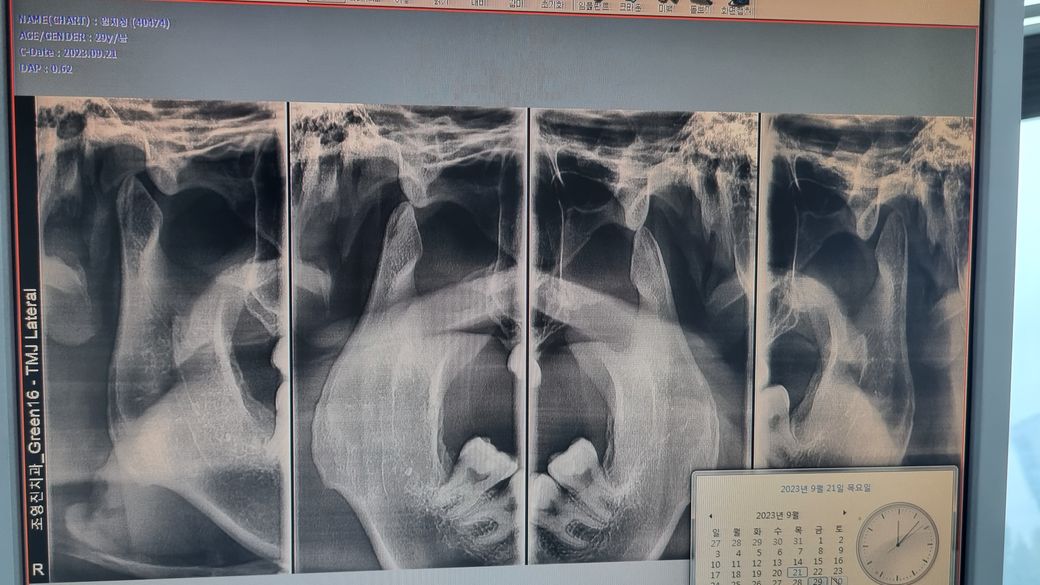

제 턱 관절이 많이 심각한 상태인가요 ?

진료 받은 변원에서는 스플린트를 필수로 해야될 상태라고 하셔서요

턱관절이 많이 닳아져 잇긴한거 같습니다. 불편하시면 턱관절 장치를 하시는게 좋을것같습니다.

x ray 사진만으로 스플린트를 필수적으로 해야 하는 지는 알 수 없습니다. 스플린트 치료는 입을 크게 안벌리고 딱딱한 것 씹지 않고 약물 치료 후에도 효과가 없을 경우에 합니다. 교정으로 턱뼈 자체는 교정이 안되며 치아 배열이 바뀌면 안면외모가 변하는 수는 많습니다.

사진상 아래턱관절 뼈가 약간 마모되어 뾰족해진 상태입니다.

턱관절 치료를 위해 스플린트 치료를 권유받으신 것 같습니다. 스플린트의 경우 턱관절 질환을 치료할 수 있는 효과적인 방법 중의 하나입니다.

치아의 교합(교정)과 턱관절은 서로 영향을 주고 받습니다. 교정을 통해 턱관절이 개선될 수도 있고 턱관절 개선을 통해 교합이 맞춰질 수도 있습니다. 악영향도 서로 주고 받습니다. 턱관절이 안 좋으면 교합도 안 좋아지고 그럴 수 있습니다 .